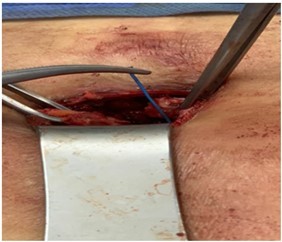

d) Excision of the track we usually find the offending wire(s) at the base of the track (Figure 2)

Figure 2.One of the offending pacing wires found adjacent to back of the xyphoid process. It is held with forceps.

One of the offending pacing wires found adjacent to back of the xyphoid process. It is held with forceps.